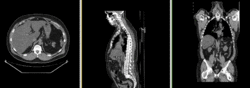

Image:RegLib_C08_unregistered.png|Original unregistered CT images.

Image:RegLib_C08_PET-CT_AnimGif.gif|Automated Affine alignment (RegisterImages) removes global differences. Differences due to posture and breathing remain.

Image:RegLib_C08_PET-CT_AnimGif_BSpl2_ResCrop.gif‎|BSpline registration of full volumes brings some correction but is distracted by the strong differences in head position.

Image:RegLib_C08_PET-CT_AnimGif_BSpl2_ResCrop.gif‎|After BSpline registration of cropped volumes, i.e. registering thoracic and abdominal regions only produces good results.